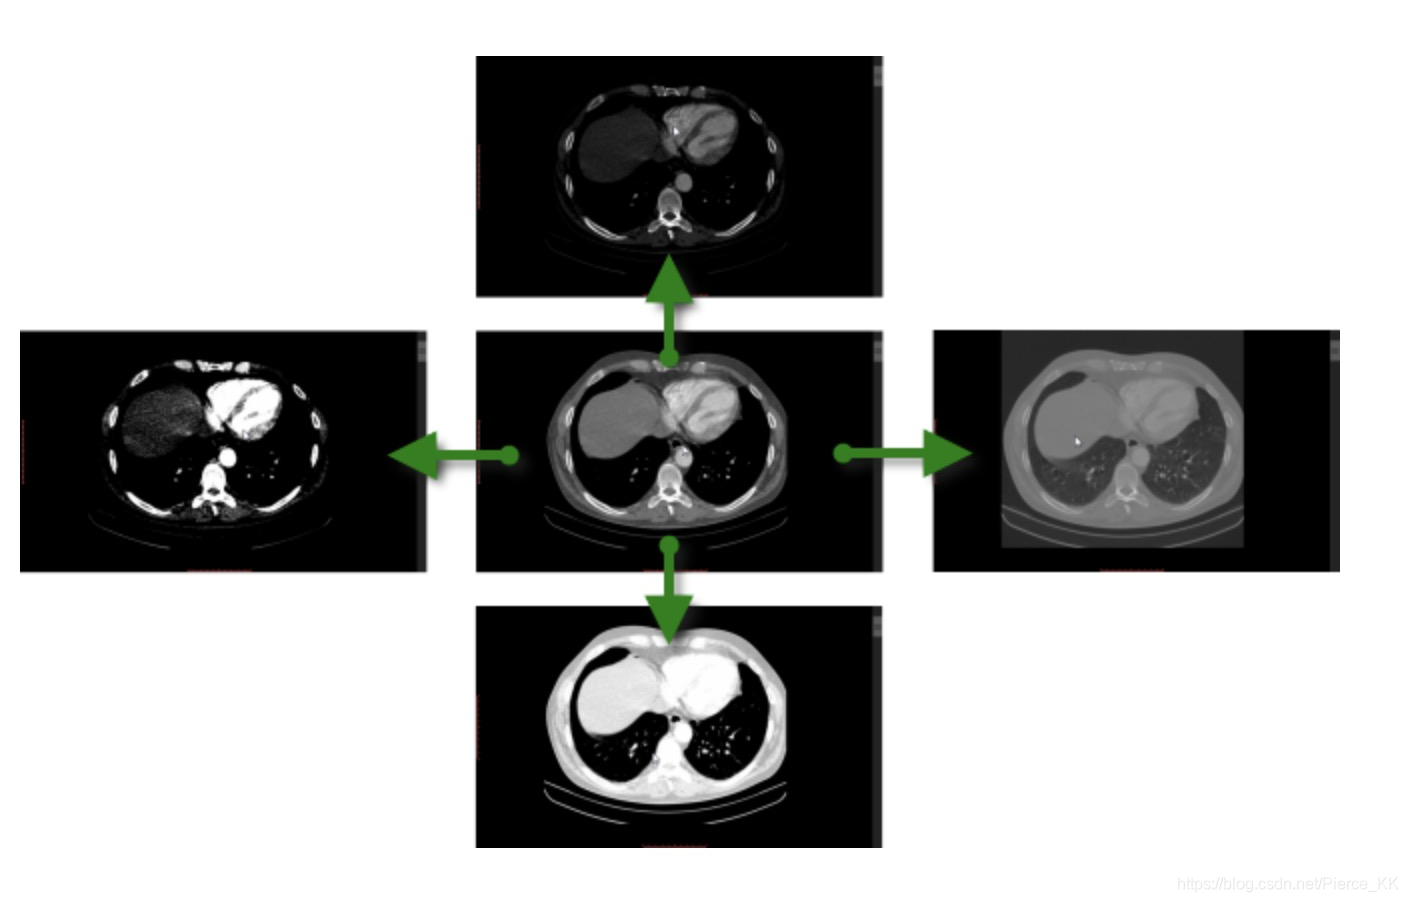

下面这张图表示出了两组对应概念之间的一些联系:

ok , 那么接下来, 我们来看细看 window level 和 window width 这两个概念。

When the window level is decreased the CT image will be brighter and vice versa.

他与图像的亮度相关, 当你降低 window level 的值, 你的CT图像的亮度就会增加,

window width 代表的是你的CT图像中 所包含的CT值的范围;

一个较宽的或者说是 较大的winidow width, 其会包含很多的 CT值(HU值),

因此,要在结构上发生 由黑到白,或者说是由暗到亮的transiton, 要将 window width的值限制在

一个较小的范围内(narrow) , 最好是一个小于1000的范围之内。

要注意, 使用一个较宽的, 包含了所有CT值的 window width 会导致各个组织之间的界限变的

非常模糊